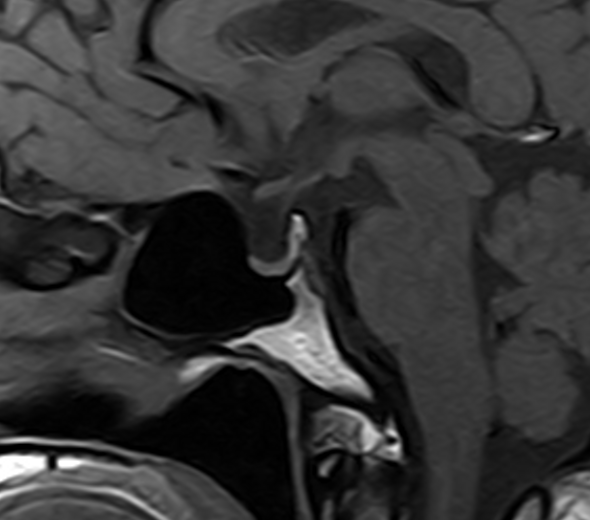

垂体-T1